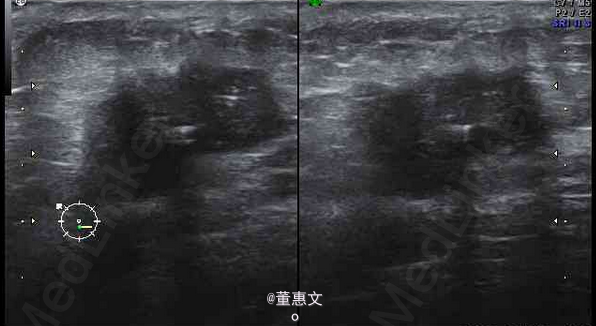

女,50岁,因3月前无意中发现右侧乳腺外下象限肿块前来就诊

无疼痛及皮肤破溃,活动度差,五畏寒发热。无胸痛及其他不适。 辅查超声

右乳腺癌 处理:手术配合放疗化疗